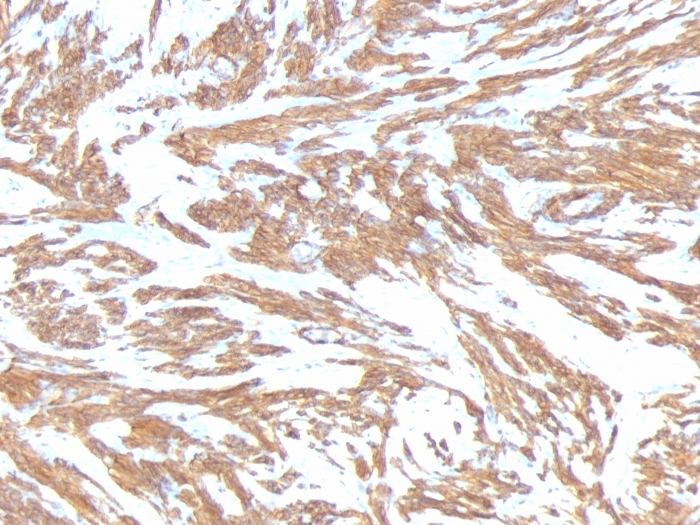

Formalin-fixed, paraffin-embedded human Leiomyosarcoma stained with Smooth Muscle Actin Monoclonal Antibody (ACTA2/791).

Actin is a major component of the cytoskeleton and is present in most cell types. It is highly specific to actin from smooth muscles. This MAb does not stain cardiac or skeletal muscle; however, it does stain myofibroblasts and myoepithelial cells. This antibody could be used together with anti-muscle specific actin and myogenin in making a diagnosis of smooth muscle and skeletal muscle tumors. In most cases of rhabdomyosarcoma, this antibody yields negative results whereas anti-muscle specific actin and myogenin are positive. Leiomyosarcomas are positive only with anti-muscle specific actin and anti-smooth muscle actin and are negative with anti-myogenin.